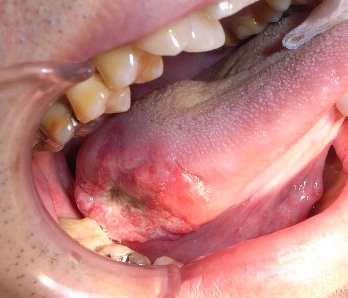

手術前

口の中にがんができるの?

口の中にできるがんを口腔がんと呼びます。口腔がんのうちの約9割はいわゆる癌で、できる場所によって舌癌、歯茎にできる歯肉癌、頬にできる頬粘膜癌、口底癌などがあります。これらの癌は、通常は、手術によって治しますが、中には癌が進行して手術できない人や手術しても大きな障害が残る可能性の高い人、手術拒否した人に対して、当科では2006年から選択動注化学(放射線)療法を行っています。